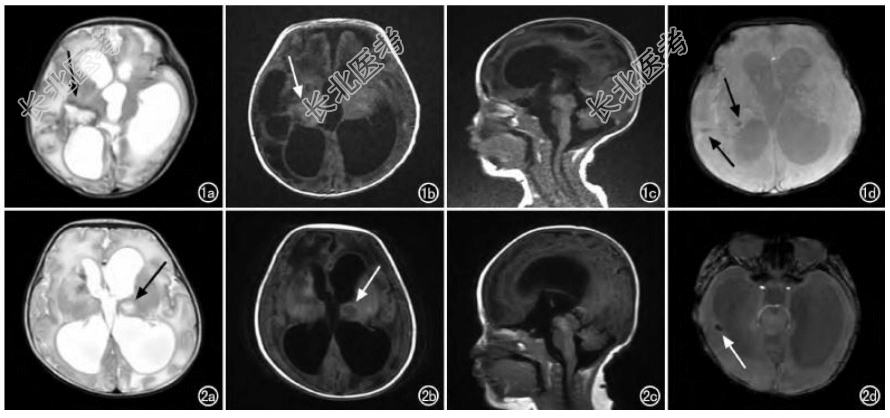

- [材料题] 患儿a,女,30天,双胞胎姐姐,胎龄35周,因胎膜早破剖宫产出生,出生时体重1.44KG,羊水清,无窒息抢救史,出生后aPGaR评分为10分。于外院行眼底检查发现双眼视网膜病变,遂来我院检查,眼底检查提示“右眼弓形虫病变?左眼早产儿视网膜病变”,查体:头围32cm,骨缝增宽,前囟饱满,全身轻度花斑纹,其他无异常。否认发病前14天内曾接触活禽或野生动物。MRI:左侧侧脑室前角旁见斑片状短T1、长T2信号;右侧侧脑室后角前方见片状短/长T1、长T2信号,边缘见环状短T2信号;双侧额叶、右侧顶颞枕叶见大片状长T1、长T2信号。透明隔腔、双侧侧脑室、第三脑室、第四脑室扩大。扩散加权成像示右侧基底节区边缘环形高信号、中央低信号病灶,大小约57MM×64MM。磁敏感成像示左侧侧脑室前角旁、右侧侧脑室后角前方局部斑点状相位图、幅度图低信号(图1)。

患儿B,女,51天,双胞胎妹妹,出生体重1.7KG。因早产儿眼底复查来我院门诊就诊,眼底检查发现右眼可疑弓形虫感染病灶。眼科检查:双眼有追光,球结膜无充血,角膜透明,前房清,瞳孔药物性散大,直径约7MM,晶状体透明。体格检查:前囟饱满,大小约25MM×25MM,双肺呼吸音粗,无啰音,四肢肌张力正常。MRI:左侧丘脑见一类圆形长T1、长T2信号,大小约9MM×9MM;dWI呈中心低信号、周围高信号,边界清晰。双侧基底节见斑片状短T1、短T2信号;双侧额颞顶枕叶见片状长T1、长T2信号。双侧脑室、第三及第四脑室明显扩张;头颅SWI示右侧颞叶、右侧枕叶斑片状相位图、幅度图低信号(图2)。